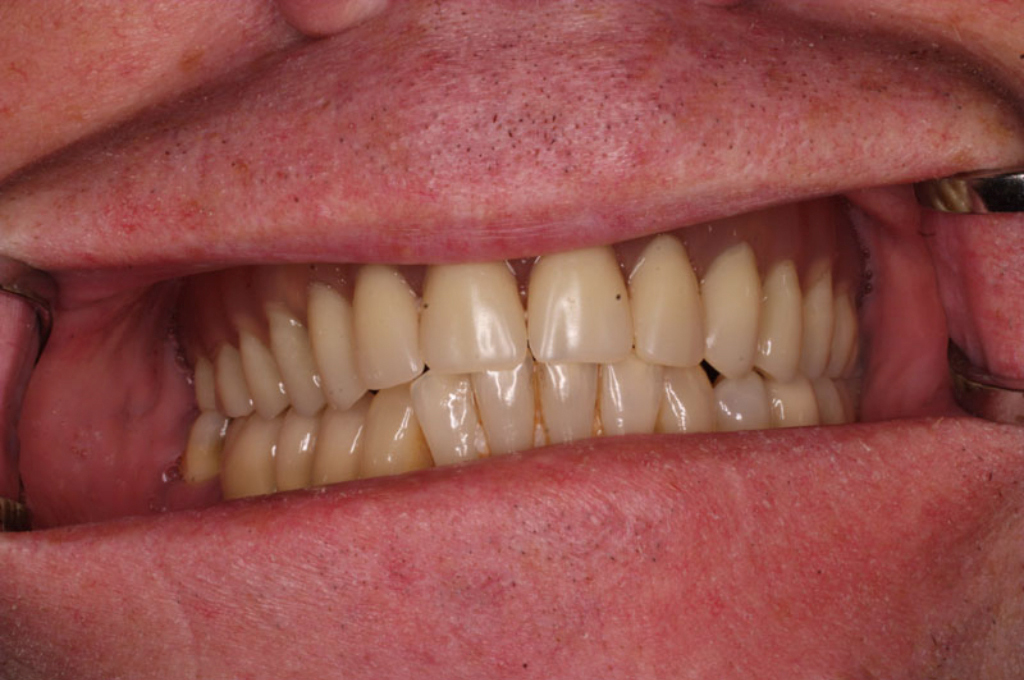

S těmito typy náhrad můžeme dosáhnout perfektní funkci, výbornou estetiku, fonetiku a současně zajistit u pacienta možnost dobré hygienickou péče a čištění, která je pro životnost implantátů velice důležitá.